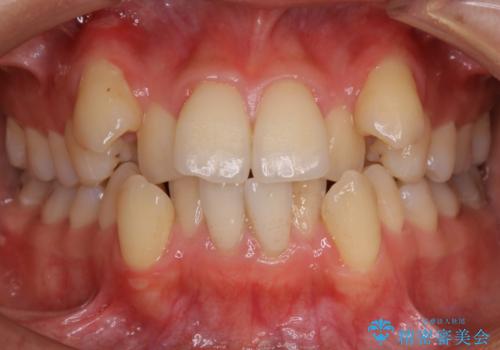

- 以前からコンプレックスだった八重歯の治療を主訴にご来院されました。

叢生の度合いが重く、抜歯が必要なケース。八重歯の部分以外には大きな問題は認められなかったため、劇的変化が起こる治療でも比較的短期間で終了することができました。